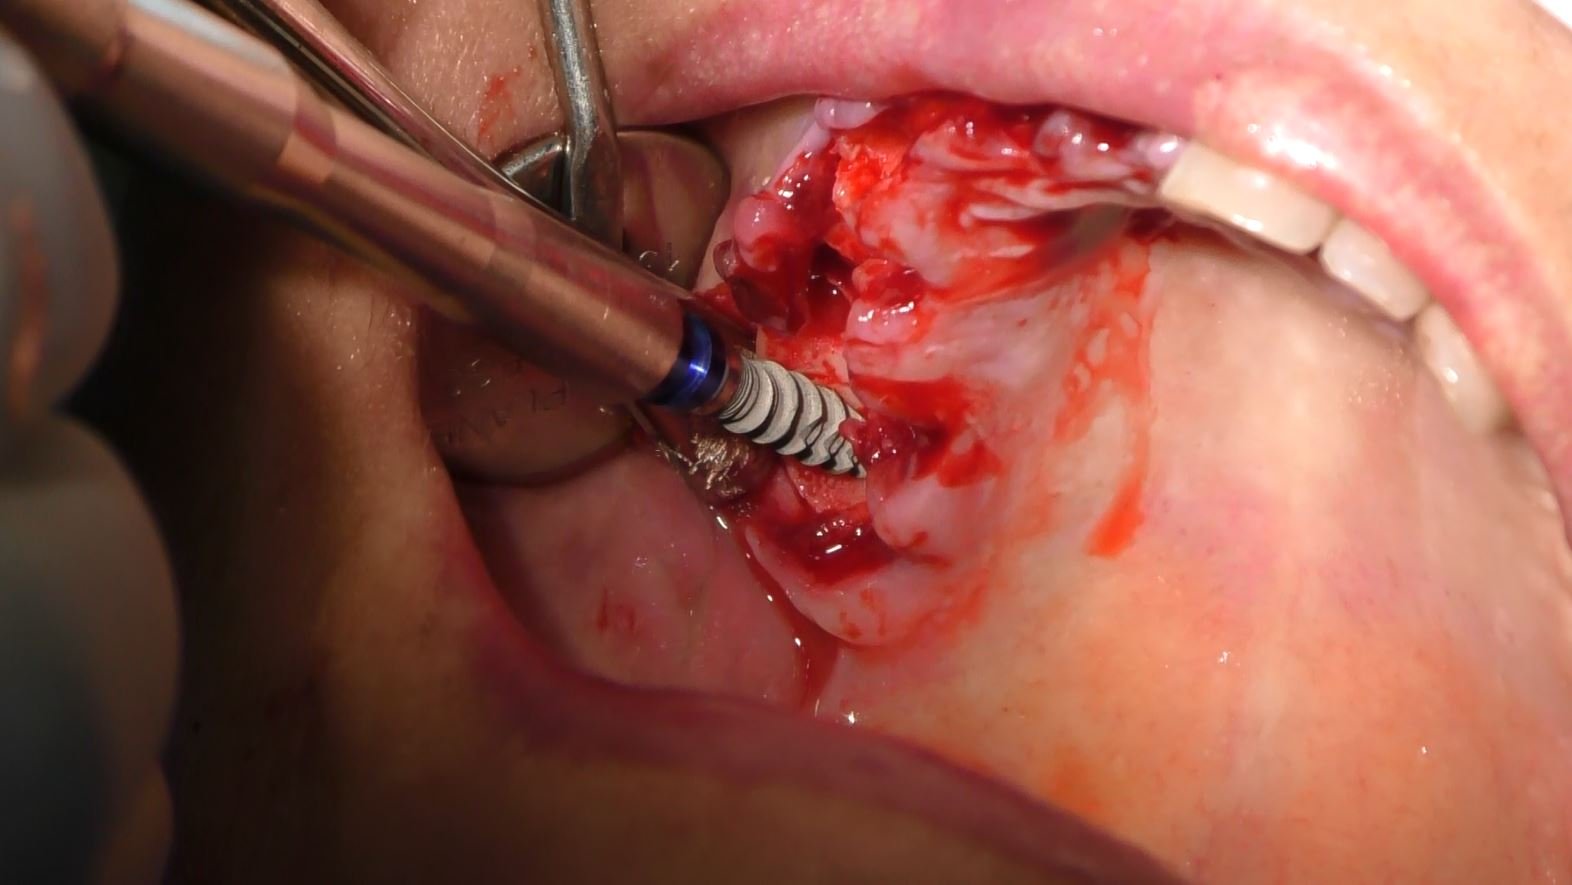

Fasi dell’Intervento:

- Valutazione Radiografica: Una valutazione dettagliata ha fornito informazioni cruciali sulla quantità di osso disponibile e sulla strategia di posizionamento degli impianti.

- Procedura Chirurgica Minimamente Invasiva: L’intervento è stato eseguito con un approccio minimamente invasivo, riducendo il trauma e accelerando il periodo di guarigione.

- Posizionamento degli Impianti Sottoperiostei: Gli impianti sono stati posizionati direttamente sulla superficie dell’osso mascellare, garantendo stabilità e supporto adeguati.

- Carico Immediato: Grazie all’implantologia sottoperiostea, il paziente ha beneficiato del carico immediato, ottenendo denti fissi funzionali in un tempo incredibilmente breve.